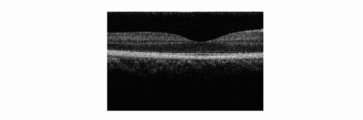

• Fig. 4A shows an OCT image according to the first embodiment.

• Fig. 4B shows the OCT image according to the first embodiment.

• Fig. 4C shows the OCT image according to the first embodiment.

• Fig. 4D shows an OCT image when an optical filter is not provided.

• signal processing including a Fourrier transformation processing operation is performed on the basis of data of the measurement, three OCT images are obtained as shown in Fig. 4.

• the interference signals, which influence the crosstalk are converted into OCT images, as shown in Fig. 4D, an unclear image that is superimposed by a portion of another beam image as a noise component is formed.

• OCT images formed by a plurality of beams, are such that measuring signals for forming tomographic images having reduced noise components can be obtained at a high speed with a sensor array having a minimum number of pixels.